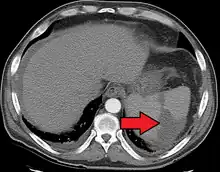

| Splenic infarct seen on CT | |

An abdominal CT scan is the most commonly used modality to confirm the diagnosis,[3] although abdominal ultrasound can also contribute.[5][6][7]